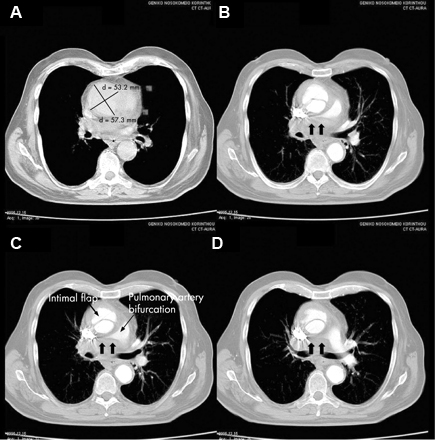

[Figure caption and citation for the preceding image starts]: CT of a 71-year-old man showing type II dissecting aneurysm of the ascending aorta. Haematoma around the proximal segment of the ascending aorta (panels A-D) compressed the right pulmonary artery, almost occluding its patency and limiting the perfusion of the reciprocal lung [Citation ends].

Result

intimal flap in acute and chronic dissection; in chronic dissection the flap may be thickened and there may be evidence of calcification and fewer periaortic reactive changes